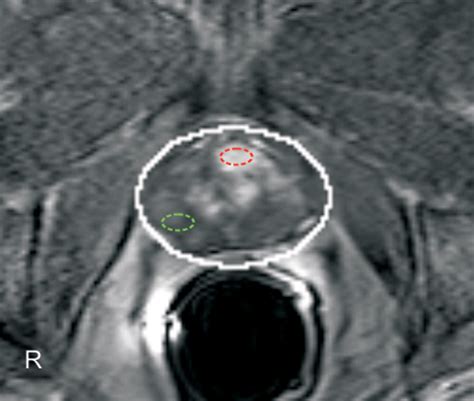

Computer-Aided Diagnosis in Multiparametric MRI of the Prostate: An ...

• Multiparametric MRI (mpMRI): This technique combines multiple MRI sequences, including T2-weighted imaging, diffusion-weighted imaging (DWI), and dynamic contrast-enhanced (DCE) imaging, to provide a comprehensive evaluation of the prostate.

• Prostate Imaging Reporting and Data System (PI-RADS): This standardized reporting system helps radiologists interpret MRI findings and classify the likelihood of clinically significant prostate cancer.